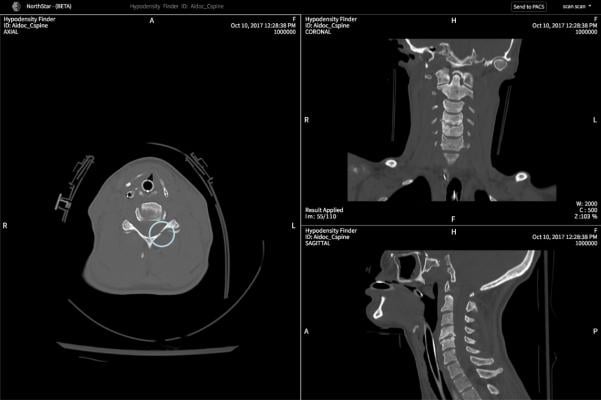

June 20, 2019 — Advanced visualization and artificial intelligence (AI) technology provider TeraRecon has successfully completed a U.S. Food and Drug Administration (FDA) regulatory review of its Northstar AI Results Explorer. TeraRecon said the technology and the determination are both firsts-of-kind in the medical imaging industry. Northstar is designed to work alongside the company’s EnvoyAI interoperability platform, which includes FDA-cleared third-party content listed on its EnvoyAI Exchange marketplace.

The Northstar AI Results Explorer provides an engaging physician user experience that can be integrated into the clinical systems already used throughout the health enterprise. Now with full commercial availability, Northstar can provide physicians a way to accept, reject and interact with AI-derived findings. Through the EnvoyAI marketplace, health systems can enter into a single contractual agreement and confidently run algorithms interchangeably, with a single two-hour software installation.

TeraRecon maintains stringent processes, documentation and quality systems across its design, development and business operations. The FDA has determined that the Northstar AI Results Explorer is exempt from Class II premarket notification requirements, and therefore is considered a Class I medical device alongside their existing Class I EnvoyAI platform.